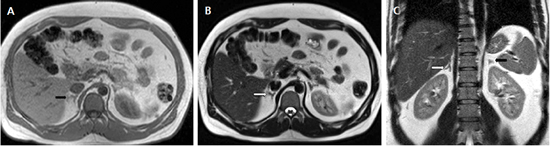

En la TC no contrastada las glándulas suprarrenales normales son homogéneas y simétricas, con una densidad muy similar a la del parénquima renal adyacente (Figura 1 a). Con un medio de contraste ev la glándula suprarrenal se opacifica en forma homogénea, similar al hígado o al bazo (Figura 1 b). Si la cantidad de tejido adiposo retroperitoneal es abundante las glándulas suprarrenales pueden aparecer enteramente rodeadas por grasa y su delimitación es más fácil (Figura 2 a); lo inverso ocurre en pacientes muy delgados con escasa grasa retroperitoneal (Figura 2 b). En RM, en secuencias ponderadas en T1 y T2 convencionales tienen una intensidad de señal homogénea, hipointensa respecto de la grasa adyacente e iso o hipointensa con respecto del parénquima hepático (Figura 3 a y b). En los cortes coronales se aprecia mejor la forma y la posición de las glándulas suprarrenales (Figura 3 c).

Figura 3. Glándula suprarrenal normal en resonancia magnética. (a) Cortes axial ponderado en T1 la señal de la glándula normal (flecha negra) es hipointensa respecto a la grasa retroperitoneal e isointensa respecto al parénquima hepático. (b) Cortes axial ponderado en T2 en que se muestra la glándula suprarrenal derecha (flecha blanca) y (c) corte coronal ponderado en T2 en que se muestra la glándula suprarrenal derecha (flecha blanca) y la glándula suprarrenal izquierda (flecha negra) con similares características de intendidad de señal. 3. Causas y prevalencia de las lesiones suprarrenales